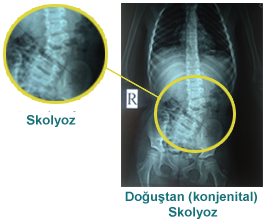

Skolyoz Tipleri

Konjenital (doğuştan) skolyoz;

Genellikle omurgadaki bir kusura veya birbirine kaynamış kaburgalara bağlıdır.

Doğuştan skolyoz hastalığı (konjenital), tıpkı çocuk felci veya beyin felci durumları sonucunda oluşan skolyoz

(omurga eğikliği) gibi omurga’nın göğüs veya bel bölgelerinde görülen yana doğru eğriliğidir.

Doğuştan (konjenital) skolyoz 0-3 yaş arasında görülür.